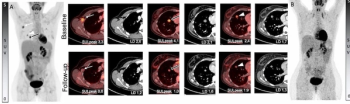

The PSMA PET agent 64Cu SAR-bisPSMA detected a higher number of prostate cancer lesions and had a significantly higher SUVmax and SUVmean than 68Ga PSMA-11 PET/CT, according to initial data from a prospective multisite study presented at the recent Society of Nuclear Medicine and Molecular Imaging (SNMMI) conference.